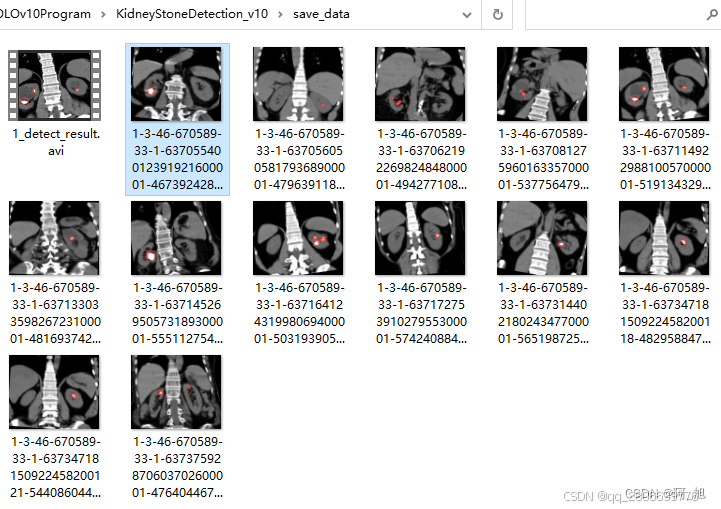

CT扫描图像的肾结石智能检测系统在医疗诊断方面提供了一种快速、准确的辅助工具,显著提高了医生识别和评估肾结石的效率。本文基于YOLOv10深度学习框架,通过1300张CT扫描的肾结石相关图片,训练了一个进行肾结石目标检测的模型,可以对CT扫描图像中的肾结石进行实时检测。并基于此模型开发了一款带UI界面的肾结石智能检测系统,更便于进行功能的展示。该系统是基于python与PyQT5开发的,支持图片、视频以及摄像头进行目标检测,并保存检测结果。本文提供了完整的Python代码和使用教程,给感兴趣的小伙伴参考学习,完整的代码资源文件获取方式见文末。

部分截图如下: